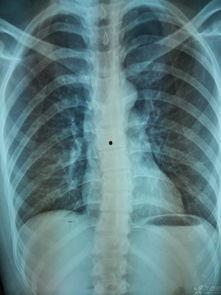

首先,让我们来认识一下脊柱的基本构成。脊柱由33块椎骨组成,分为颈椎、胸椎、腰椎、骶椎和尾椎五个部分。这些椎骨之间通过椎间盘连接,椎间盘就像弹簧一样,缓冲了脊柱在运动过程中的震动。

胸椎位于颈椎下方,共有12块椎骨。它们与肋骨相连,构成了胸廓,保护着心脏和肺部等重要器官。胸椎的椎间盘较厚,稳定性较好。视频讲解中会详细展示胸椎的结构,以及如何通过锻炼来增强胸椎的稳定性。

腰椎位于脊柱的下方,共有5块椎骨。它们承受着身体大部分的重量,因此非常容易受到损伤。腰椎的椎间盘较厚,但仍然需要我们注意保护。视频讲解会教你如何正确弯腰、提重物,以及如何通过锻炼来增强腰椎的力量。

骶椎和尾椎位于脊柱的最下方,骶椎由5块椎骨融合而成,尾椎由4块椎骨融合而成。它们与骨盆相连,支撑着整个身体。虽然骶椎和尾椎的体积较小,但它们在维持身体平衡和稳定方面起着重要作用。视频讲解中会展示骶椎和尾椎的结构,以及如何通过锻炼来增强它们的稳定性。